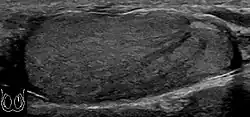

Embryonal cell carcinomas, a more aggressive tumor than seminoma usually occurs in men in their 30s. Although it is the second most common testicular tumor after seminoma, pure embryonal cell carcinoma is rare and constitutes only about 3 percent of the nonseminomatous germ cell tumors. Most of the cases occur in combination with other cell types. At ultrasound, embryonal cell carcinomas are predominantly hypoechoic lesions with ill-defined margins and an inhomogeneous echotexture. Echogenic foci due to hemorrhage, calcification, or fibrosis are commonly seen. Twenty percent of embryonal cell carcinomas have cystic components. The tumor may invade into the tunica albuginea resulting in contour distortion of the testis [Fig. 4].